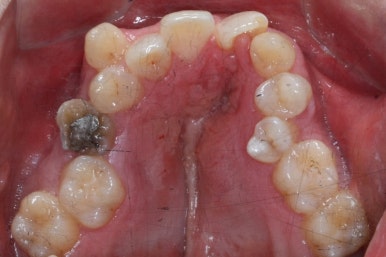

치료 전과 가장 최근의 사진을 비교해 보겠습니다.

좌측이 부산구순구개열 전, 우측이 가장 최근의 사진들입니다.

거꾸로 물리던 앞니가 개선되었습니다.

좁아져 있고 찌그러진 위턱뼈의 형태가 개선되었습니다.

영구치 개수가 모자라는 선천결손이 있었지만 아랫니도 개수를 맞춰줌으로써 치아의 맞물림도 상당히 좋아졌습니다.